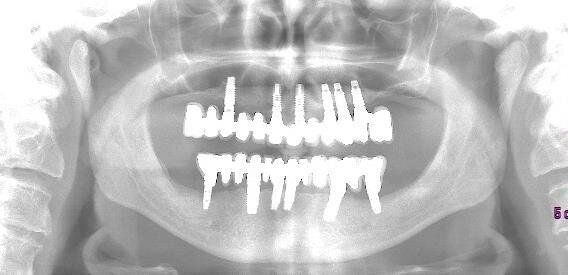

Si effettua solo una ortopantomografia, nessun sondaggio, nessuna valutazione parodontale. Si estraggono i denti, si inseriscono gli impianti, ma… non ci stanno! Tra mille problemi tecnici, diversi operatori e molteplici rifacimenti l’implanto-protesi viene finalizzata dopo oltre 3 anni, ma determina problemi masticatori. Alcune corone si rompono, non è funzionale (il paziente non si riesce a mangiare), fa male, ma soprattutto non piace all’anziano signore.

Inoltre, la protesi traumatizza con le parti metalliche i tessuti molli e la lingua, le corone sono inclinate in senso vestibolare e non occludono alla perfezione. L’overjet è ampio ed è presente un morso aperto anteriore, con trauma sui posteriori. Si vedono i colletti metallici degli impianti, metallo compare negli spazi interprossimali (corone ed impianti non sono in linea)(Figg. 2-4).